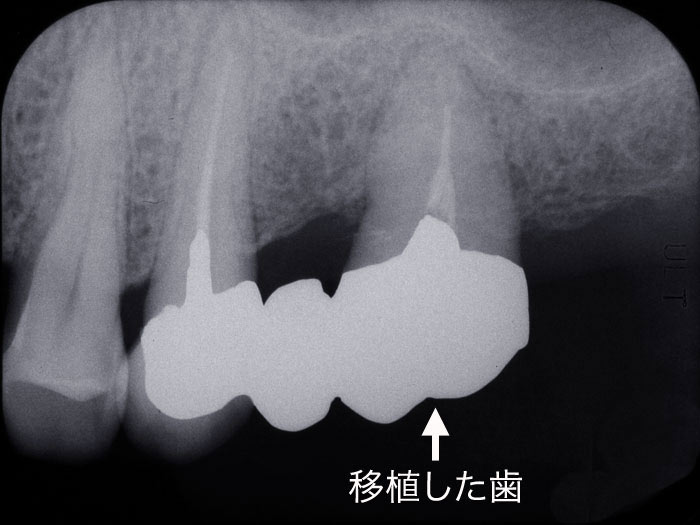

歯が無くなってしまったところに噛み合わせに関係のない親知らずなどを移植することが出来ます。20年以上前からある方法ですが未だに一般的ではなく手掛ける歯科医も知っている患者さんも少ないのが現状です。しかし自分の歯であれば問題なく他の場所で元からそこにあったように機能させることができ、沢山の良好な経過がでてきています。インプラントを考えるのと同時に自分の歯を移植できるかどうかを考える必要があります。移植できるケースとできないケースとがありますが、親知らずであっても自分の歯を一本でも有効に使うことが大切であると考えています。